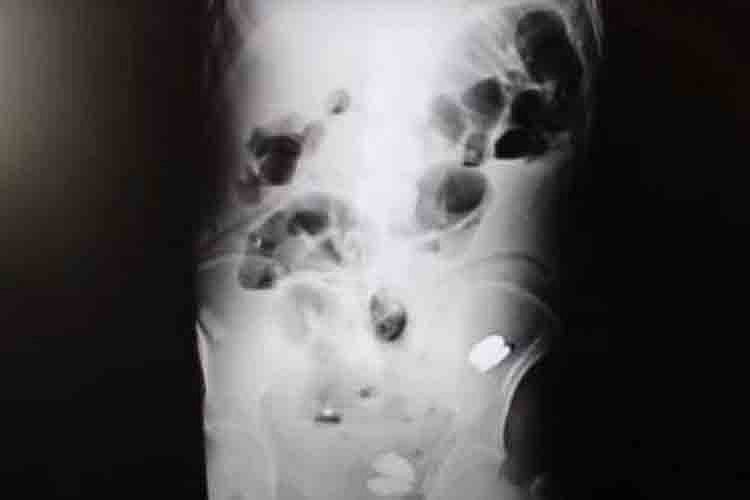

துருக்கி நாட்டைச் சேர்ந்த 35 வயது இளைஞருக்கு சில நாட்களாக கடும் வயிற்று வலி இருந்து வந்துள்ளது. இதையடுத்து அவர் மருத்துவமனையில் சிகிச்சைக்காகச் சென்றுள்ளார். அப்போது மருத்துவர்கள் பரிசோதனை செய்து ஸ்கேன் எடுத்துபார்த்தபோது இளைஞரின் வயிற்றுக்குள் நாணயங்கள், பேட்டரிகள், கற்கள் உள்ளிட்ட பல பொருட்கள் இருந்தை கண்டு அதிர்ச்சியடைந்துள்ளனர்.

பின்னர் உடனே அவருக்கு அறுவை சிகிச்சை செய்ய மருத்துவக்குழு முடிவு செய்துள்ளது. இதையடுத்து அவரது வயிற்றை அறுவை சிகிச்சை செய்தபோது அதில் 233 நாணயங்கள் இருந்தை பார்த்து மருத்துவர்கள் அதிர்ச்சியடைந்துள்ளனர்.

பின்னர் வயிற்றில் இருந்த அனைத்து நாணயங்கள் மற்றும் நகங்கள், பேட்டரிகள், கற்கள் ஆகியவற்றையும் மருத்துவர்கள் பத்திரமாக வெளியே எடுத்துள்ளனர். தற்போது அறுவை சிகிச்சைக்கு பிறகு அந்த இளைஞர் நலமுடன் இருப்பதாக மருத்துவர்கள் தெரிவித்துள்ளனர்.

இந்த அறுவை சிகிச்சை குறித்துப் பேசிய மருத்துவர் பெனிசி, "அறுவை சிகிச்சையின் போது ஒன்று அல்லது இரண்டு நகங்கள் நாங்கள் முதலில் பார்த்தோம். பிறகு வயிற்றுக்குள் இருந்த பெரிய குடலில் இரண்டு கற்கள் இருந்தை கண்டு அதிர்ச்சியடைந்தோம்.

மேலும் பேட்டரிகள், நகங்கள், 233 நாணயங்கள் இருந்தை கண்டு நாங்கள் பீதியடைந்தோம். பிறகு அனைத்தையும் பத்திரமாக வயிற்றிலிருந்து வெளியே எடுத்தோம். பெரியவர்களுக்கு இந்த மாதிரியான நிலையை நாங்கள் இதுவரை பார்த்தது இல்லை.